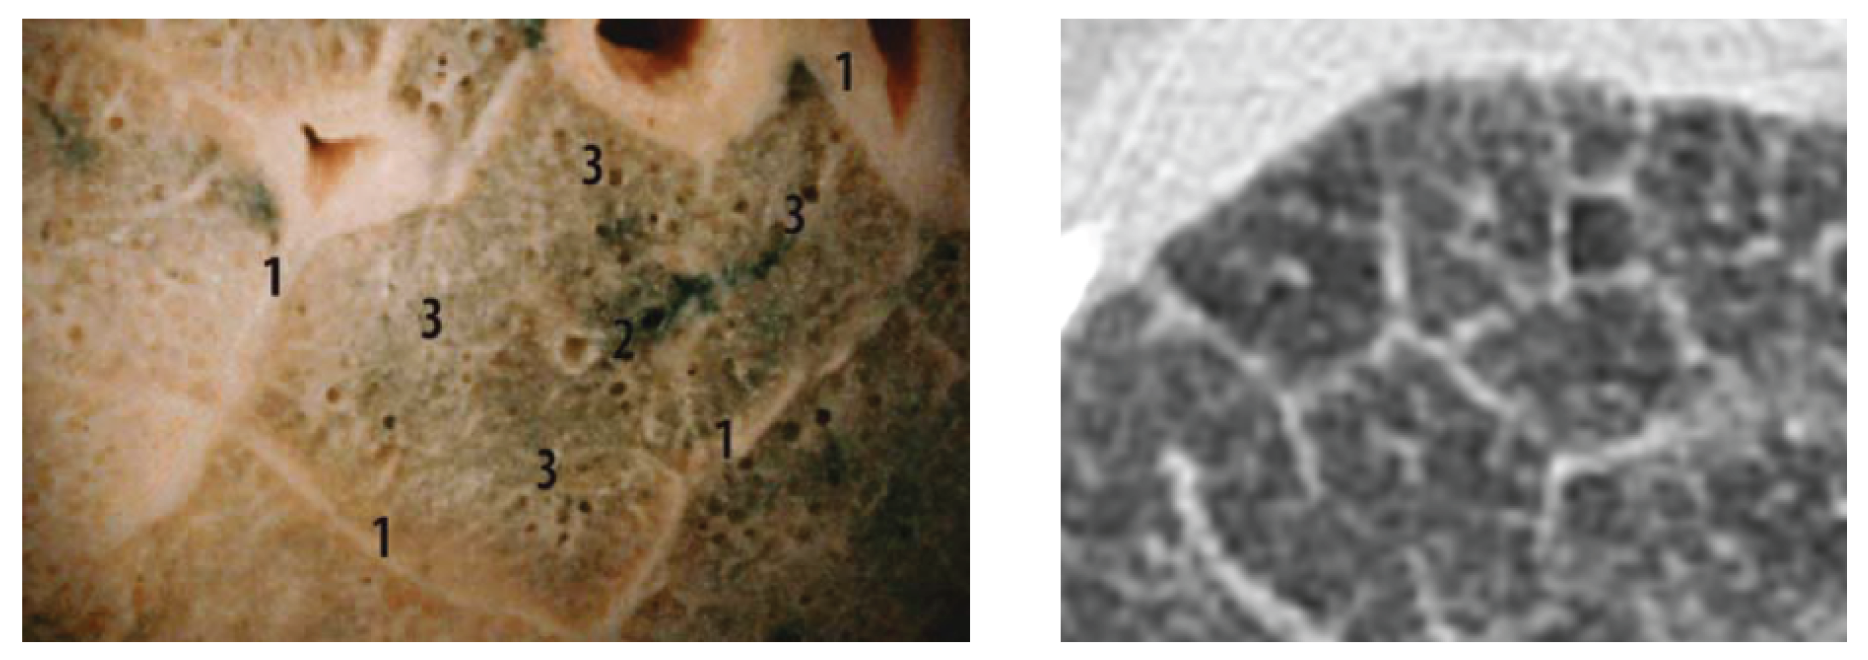

A comparison of the obtained images after improvements/filtering (see Figure 8) with the lung lobulus anatomy is shown in Figure 9, where the left image represents a cadaver section and the right one a high resolution computer tomography (HRCT) image. It is quite obvious that we managed to achieve a completely adequate imaging method that makes lung tissue visible in an excellent way.

Figure 9. Lung lobulus anatomy: cadaver section of the lungs with visible lung lobules with 1 for interlobular septa, 2 for central bronchioles (left), HRCT section of the patient with interstitial edema, where septas and lobules are clearly visible (right) Verschakelen (2007).